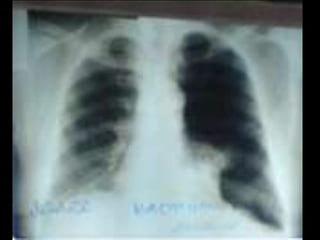

C’est un téléthorax de face objectivant une volumineuse opacité de tonalité hydrique hilaire gauche Forme : grossièrement ovalaire • Taille : mesure 6 à 8 cm de grand axe • Limites : interne noyée dans le médiastin et se raccordant à angle aigue avec le bord gauche du médiastin. • Limite externe flou irrégulière réalisant l’aspect en patte de crabe • Plage : hétérogène par la présence de broncho gramme aérien • Index cardio thoracique, les culs de sacs pleuraux sont libres • On note une petite opacité de tonalité calcique se projetant sur le lobe supérieur du poumon droit • Conclusion : gros hile tumorale malin gauche évoquant un cancer bronchique proximal • Pas de diagnostic différentiel • CAT : bilan d’extension:fibroscopie bronchique, TDM thoraco- abdominale, échographie abdomino-pelvienne et scintigraphie osseuse